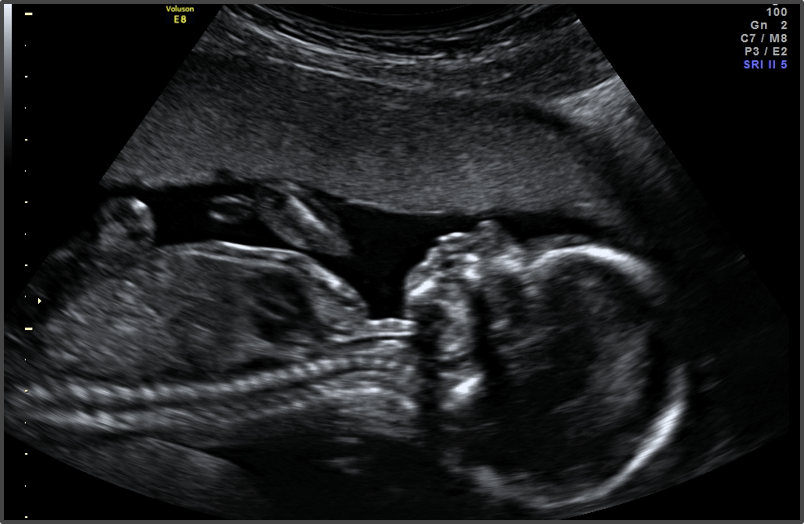

Pregnancy Calculator - Week 17

Your baby is the size of an onion.

Approx Baby Weight: 140g

Approx Baby Size: 13 cm

Baby Development

The baby’s bones are strengthening, and hair starts to grow.